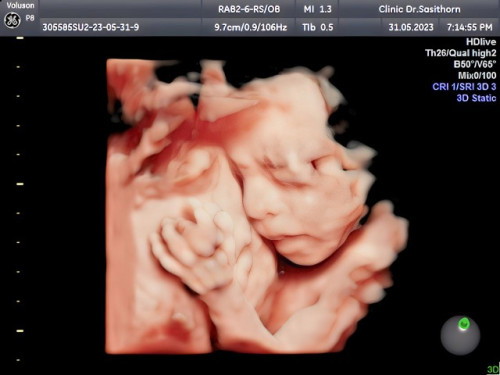

ป้าหมอบอกน้องตัวเล็ก25w

น้อง25wนํ้าหนัก679 หมอบอกน้องค่อนข้างตัวเล็กไปรอบหน้านํ้าหนักต้องดีกว่านี้ แม่พยายามบำรุงอยู่แต่ก็ไม่เป็นผล กินเยอะก็หายใจไม่สะดวกอยู่ยาก กินน้อยก็ไม่ลงน้อง แม่เครียดเลยค่ะตอนนี้ใครมีวีธีเพิ่มนํ้าหนักเพิ่มแก้มให้น้องบ้างรบกวนแม่ๆด้วยนะ🥹😥🙏 #ขอบคุณล่วงหน้านะคะ #ขอบคุณสำหรับคำตอบค่ะ